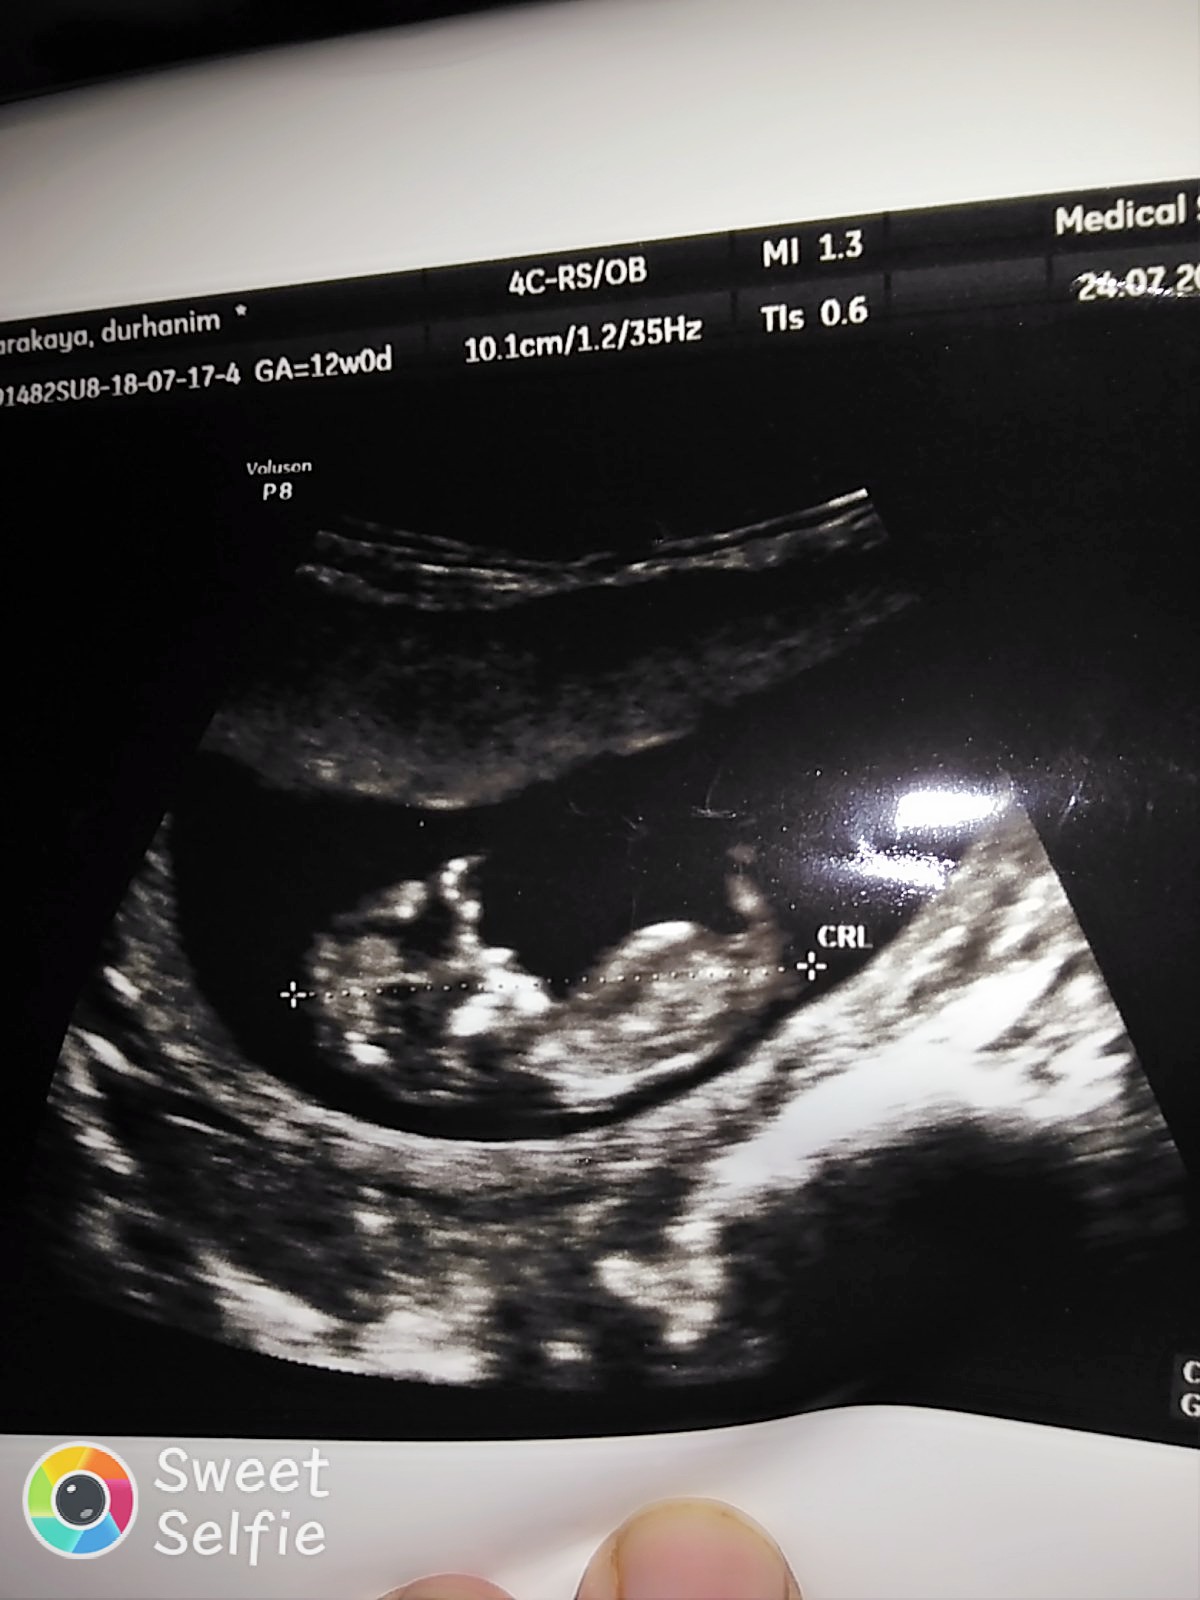

Tam net değil ama iyice yakınlaştırınca bebeğin cinsiyeti erkeğe benziyor. Tabi bebeğin cinsiyetini 20 . haftalarda net öğreneceğinizi de belirtelim.Sağlıklı gebelik geçirmeniz dileği ile.

Çok teşekkür ederim vakit ayırıp cevap verdiğiniz içinSelamlar sevgili dilara inceledim baştan aşağıya yüzde yüz kız gibi görünüyor hayırlı olsun